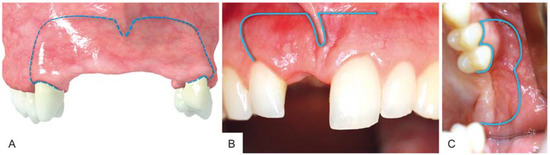

3. Surgical Procedure